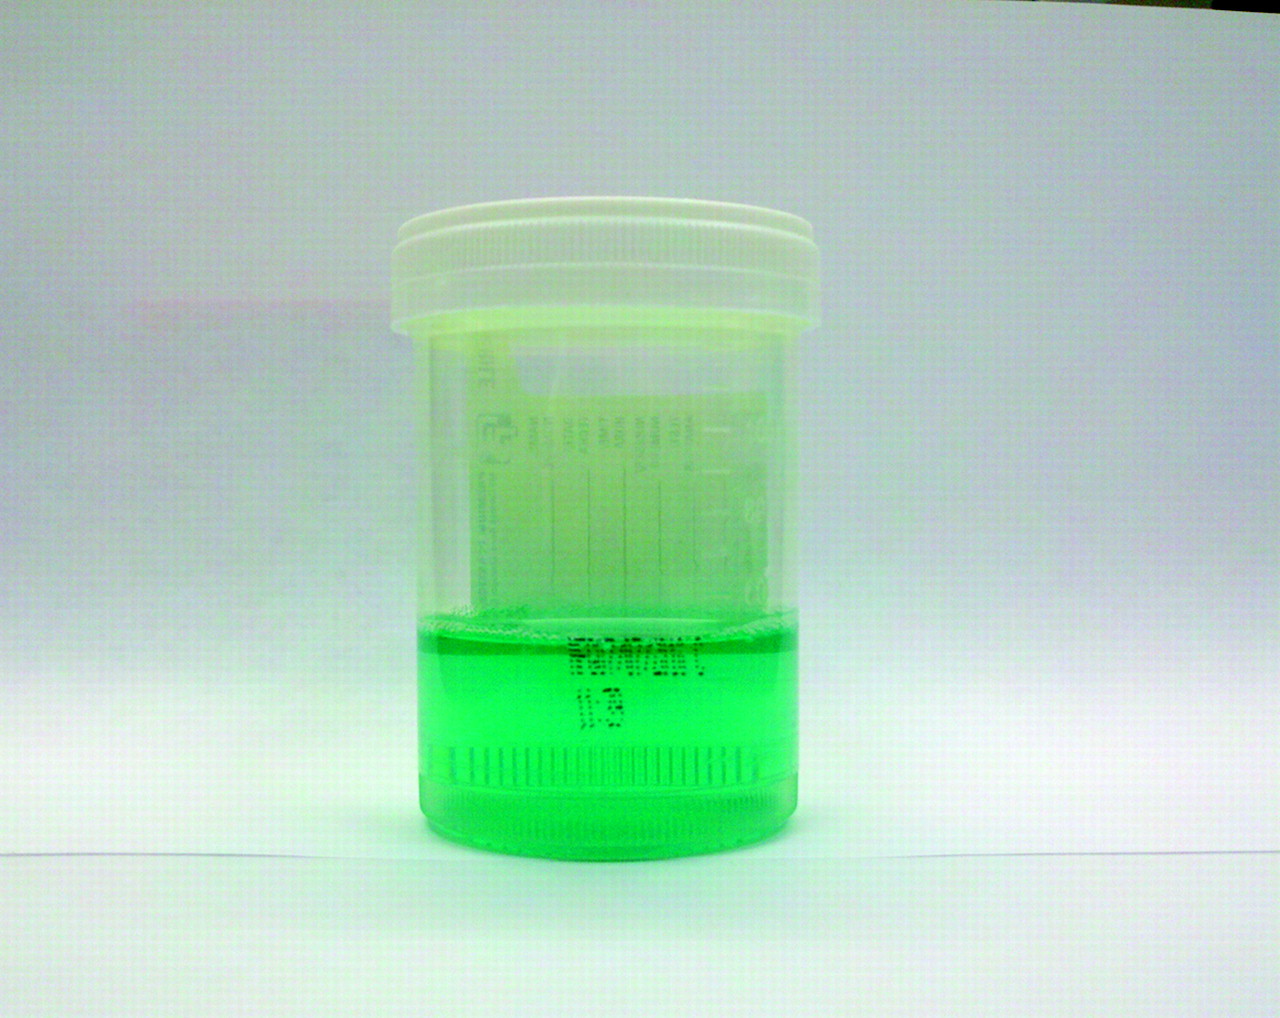

Моча (урина) — одна из биологических жидкостей в организме человека, вырабатываемая в почках в процессе фильтрации крови. С ней выводятся конечные продукты метаболизма, лекарственные и токсические вещества, другие примеси.

Их состав и концентрация влияют на окраску мочи. Кардинальное изменение цвета вызывают физиологические или патологические процессы в организме. Поэтому моча зеленого цвета не во всех случаях является признаком болезни.

Установить это можно с помощью анализа урины. Цвет мочи является свойством, которое определяют визуально.

Естественный оттенок мочи – светло-желтый (соломенный). Он может быть немного светлее или темнее. Это зависит от уровня насыщенности клеток организма водой.

Светло-зеленая моча появляется при наличии растительных пигментов и синтетических добавок, употребляемых с едой, приеме лекарственных веществ. Также урина становится зеленого цвета от индикана — вещества, вырабатываемого в организме при некоторых патологиях. Его находят в анализе мочи. Он является важным симптомом для диагностирования болезней.